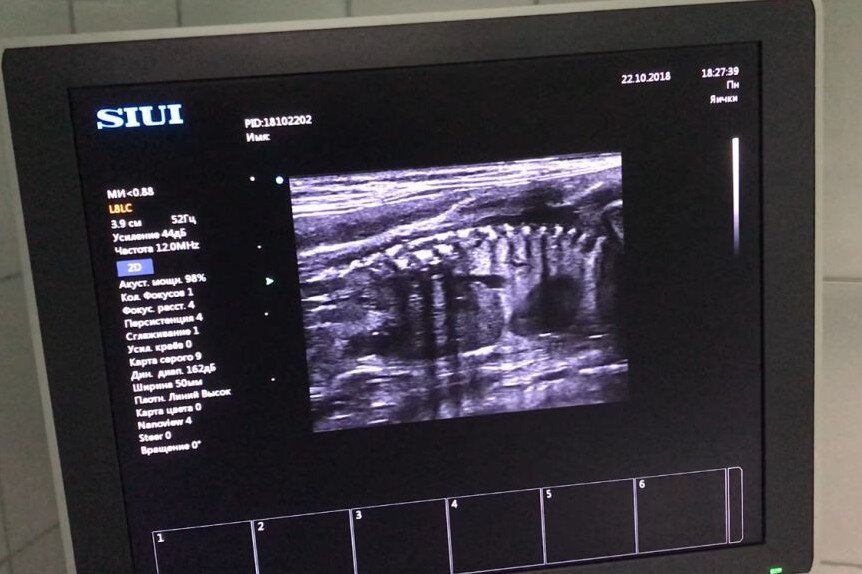

УЗИ беременности кошки, срок 1 месяц

Второе УЗИ мы делали Барселоне, которой рожать довольно скоро, мы так и не смогли посчитать малышей, потому что на этом сроке уже легко ошибиться, посчитав дважды один и тот же плод. Ее срок – 50-55 дней, на этом сроке уже хорошо видны ребрышки и внутренние органы, видна дифференциация сердца на отделы.

УЗИ беременности кошки, срок 60 дней